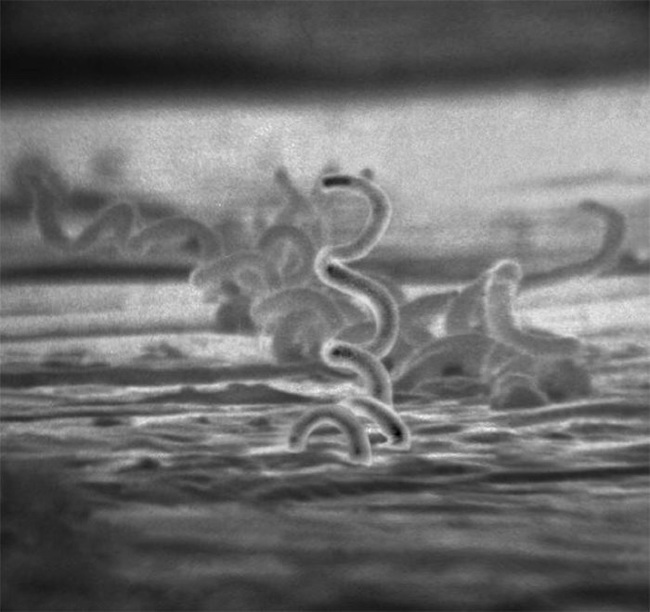

梅毒トレポネーマの電子顕微鏡写真(筆者提供、出典:Centers for Disease Control and Prevention’s Public Health Image Library)